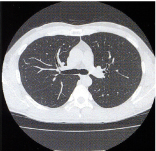

胸部撮影 -